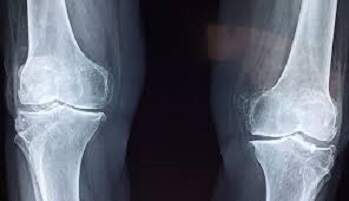

Um grupo de cientistas da Universidade Federal de Paraíba (UFPB) realiza uma pesquisa sobre o uso de um implante muito menor do que o diâmetro do fio de cabelo para tratar faturas. Por meio da liberação controlada de um fármaco chamado sinvastatina na área lesionada, o dispositivo consegue acelerar a regeneração da área lesionada.

Assim que passou no mestrado, em 2014, Kaline passou a estudar o trabalho que estava sendo desenvolvido com a sinvastatina junto com os professores e a ideia surgiu a partir dos estudos referentes às fraturas ósseas. “Identificamos, por exemplo, que no Brasil a osteoporose acomete 10 milhões de pessoas, com prevalência de 11 a 23,8% para todos os tipos de fraturas por fragilidade óssea. Sendo assim, iniciei a elaboração de um sistema que pudesse acelerar os processos reconstrutivos que eles já vinham buscando”, declara.